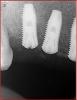

m.d.n Опубликовано 12 апреля, 2011 Поделиться Опубликовано 12 апреля, 2011 вот такая ситуация, как потом протезировать .каких ошибок надо избежать ?спасибо . Ссылка на комментарий

Bier Опубликовано 12 апреля, 2011 Поделиться Опубликовано 12 апреля, 2011 пожалуй самое сложное место это третий сегмент - кстати стандартная ошибка начинающих. По хорошему надо там переставлять имплантат или делать с консолью... Ссылка на комментарий

Bier Опубликовано 14 апреля, 2011 Поделиться Опубликовано 14 апреля, 2011 это не спасет от установки имплантата в дистальную позицию, как произошло в левом сегменте. Это часто происходит у начинающих имплантологов. Надо просто прежде чем засверливаться, посмотреть на точку предполагаемого сверления с другой стороны + использовать шаблон. Ссылка на комментарий

Dr. Surkin Опубликовано 14 апреля, 2011 Поделиться Опубликовано 14 апреля, 2011 пожалуй самое сложное место это третий сегмент - кстати стандартная ошибка начинающих. По хорошему надо там переставлять имплантат или делать с консолью... Если интегрировался, то переставлять смысла нет. Сделать с консолью. Мостики же делают И как минимум справа на передний имплантат придется индивидуальный абатмент делать. Тут еще по снимку не скажешь про язычный или щечный наклон... Ссылка на комментарий